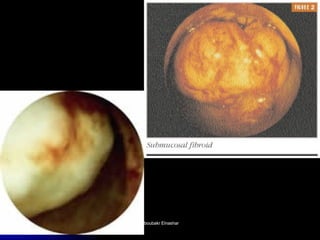

The document discusses the history and development of hysteroscopy. It began in 1869 but did not achieve routine use until improvements to optics, distension media, lighting and instruments in the 1970s-1990s allowed for office procedures without anesthesia. Today, many hysteroscopic procedures have replaced older, more invasive techniques. The document then provides details on rigid and flexible hysteroscopes, lighting sources, distension media, and diagnostic and operative uses of hysteroscopy for conditions like abnormal bleeding, infertility, uterine anomalies and assisted conception. Contraindications are also outlined.